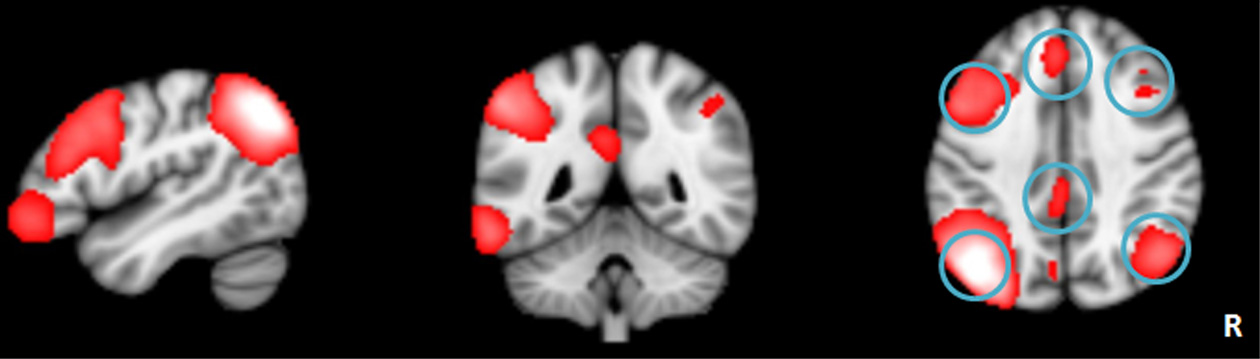

Figure 1

The left frontoparietal network identified by independent component analysis.

Results from ICA analysis

The LFPN that we obtained from our cohort of subjects includes the bilateral parietal cortex, bilateral frontal cortex, medial frontal cortex and posterior cingulate cortex (Figure 1). We obtained 20 spatial and temporal components from the ICA analysis and noted that the results from previous ICA analyses support the selection of the LFPN (Smith et al., 2009; Biswal et al., 2010). The group-level ICA was performed separately in patients and controls (Figure 3).

Network connectivity analysis of left frontoparietal network

To better understand the impact of network connectivity differences on whole-brain intrinsic connectivity, we employed network connectivity analysis to LFPN changes. We used standard image processing methods with SPM8 (http://www.fil.ion.ucl.ac.uk/spm) and the conn toolbox (http://www.nitrc.org/projects/conn) for functional connectivity and network connectivity analysis. Our pre-processing steps included correcting for motion, coregistering with the anatomic scan, normalizing into the Montreal Neurological Institute space, resampling at 2 mm3, and smoothing with a Gaussian kernel of 6 mm3 full-width at half maximum. We extracted the bold time series data for six ROIs within the LFPN obtained from the ICA analysis mentioned above. The ROIs were derived from the LFPN (centered on the MNI coordinate of the cluster peaks, and with a radius of 4 mm) (Figure 1). Prior connectivity studies have employed similar approaches to the investigation of the default mode network (DMN) (Dosenbach et al., 2007; Fair et al., 2008; Posner et al., 2013). The LFPN ROIs and their coordinates are delineated in Table 1. We correlated the time series data for each ROI region by region for each subject, producing a single 6 × 6 correlation matrix for each subject. We calculated the mean index of the LFPN by reducing each subject's 6 × 6 correlation matrix from the overall mean into a single variable that indexed the global connectivity for the LFPN including all edges. We compared the mean network connectivity index across the patient and control groups using a two-sample t-test. We also performed correlation analyses to assess the relationship between the mean connectivity of the LFPN and the language test results.

The left frontoparietal network regions.